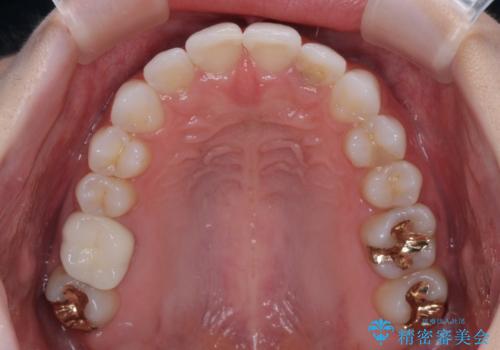

- 歯並びと虫歯をきれいにしたいとのことで来院された患者様です。

楽して短期間で歯列を整えたいとのことで、ワイヤー装置を用いて矯正治療を行い、矯正治療後に下顎の虫歯はセラミックインレー、上顎はPGAインレー(ゴールドインレー)、根管治療を行う歯についてはオールセラミッククラウンにて補綴治療を行うこととしました。

矯正治療は8ヶ月ほどで終了し、速やかに虫歯治療に移行することができました。

保険治療で用いる樹脂(コンポジットレジン)で行った虫歯治療は、周辺が変色して汚くなっていましたが、下顎はセラミックインレーで審美的に、上顎はPGAインレーで歯に負担の少ない治療を行うことができました。